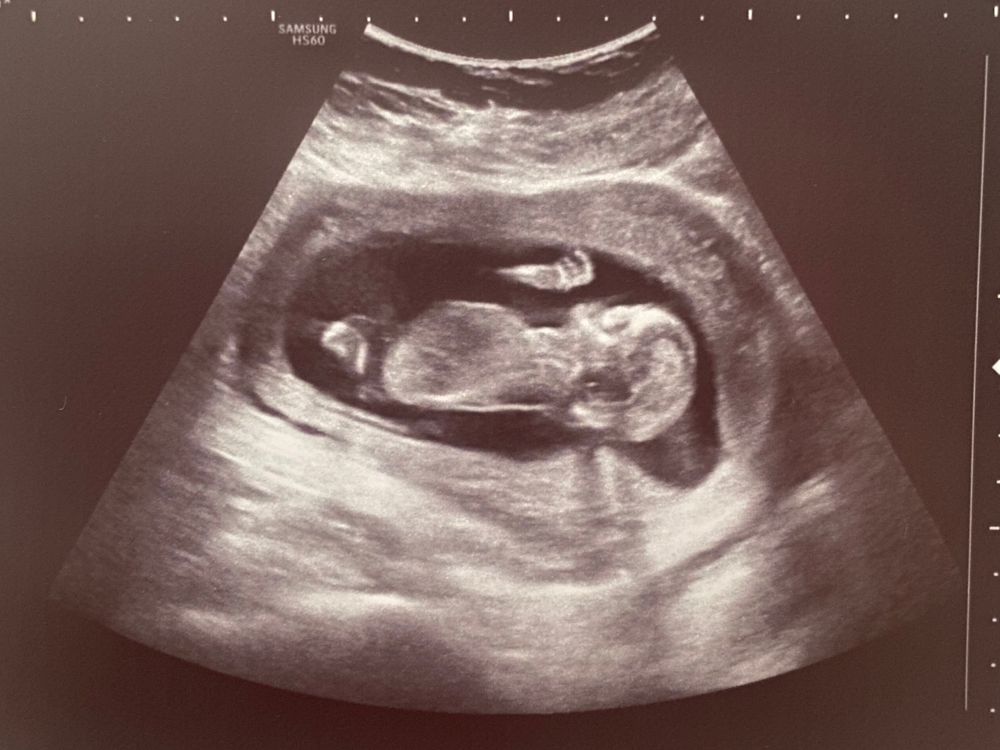

13+4 УЗИ 🤍

По скринингу 13+4, по этому узи 13+5, всё соответствует сроку, всё отлично!)

Предположили мальчика🙈

Изображение